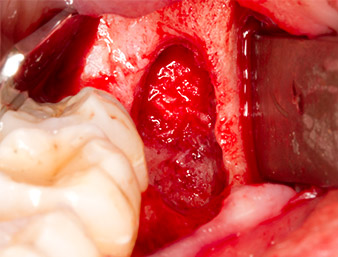

It was then possible to remove the approximately six-millimetre-long root remnant in one piece with the P1 attachment (Fig. 11).

Periapical inflamed tissue was also removed very carefully with a manual excavator. Fig. 12 shows the empty alveole with exposed inferior alveolar nerve.

Radix relicta

Fig. 11: The extracted radix relicta measures more than 6 millimetres.

inferior alveolar nerve

Fig. 12: The inferior alveolar nerve can be seen in the bottom of the alveole.